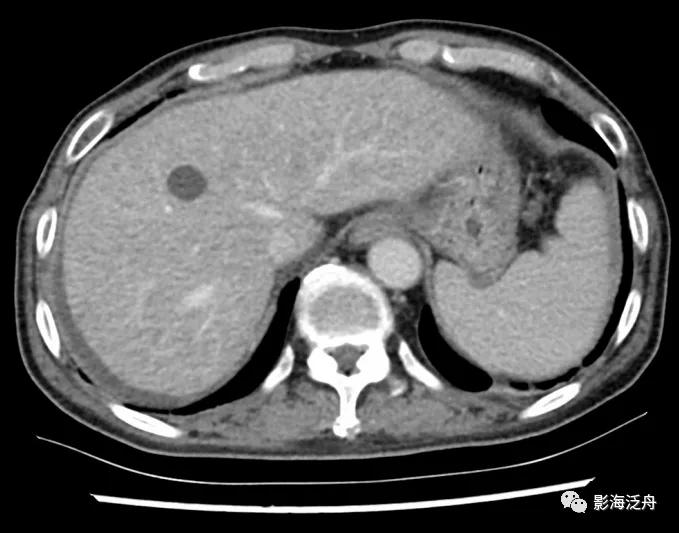

胰腺癌术后3月复查,肝周少量积液,增强门脉期肝实质密度略欠均匀,隐约可见许多细小斑点状低密度影。

同一患者,又过了3个月复查,可以比较清楚地观察到肝内有很多异常强化灶,边界不清,表明肝脏已经出现弥漫性转移。如果能够提高意识,在第一次复查时就给出异常提示或进一步检查,或许能。。。